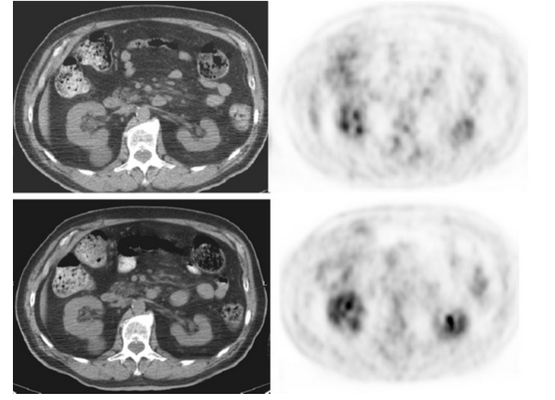

На снимках представлен 76-летний пациент с неходжкинской лимфомой: мезентериальный панникулит (МП), как результат прогрессирования патологии.

Первые четыре изображения соответствуют первичному исследованию. Вторичное ПЭТ/КТ выполнено спустя 4 месяца.

На снимках характерные находки для мезентериального панникулита без накопления 18f-FDG, что хорошо визуализируется на последующих.